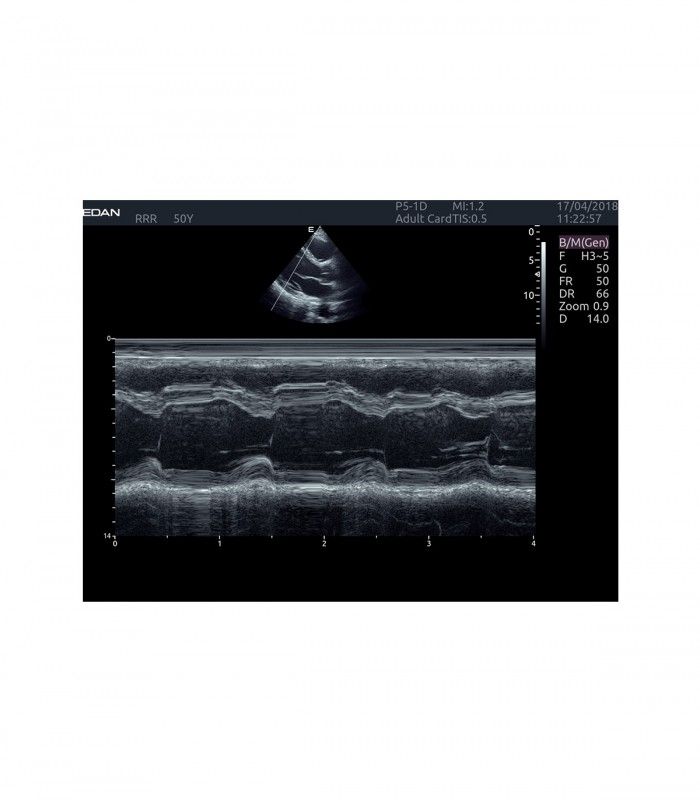

L’AX4 affiche une image claire et précise dans les différents modes grâce à de multiple technologies de traitement de l’image.

- Imagerie entièrement automatisée (modes B, couleur, doppler, M)